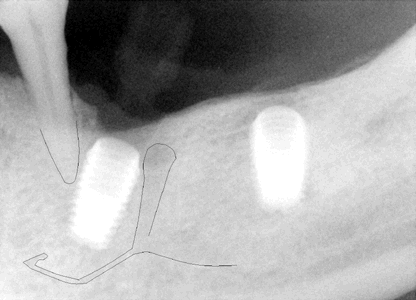

Fig.6 (left) and 7 (right) A PA was

taken immediately before implant placement (Fig.6). There are two radiolucent areas (including one being traced).

The surgeon did not see them or clearly realized that one of them is the

terminal part of the ascending mental nerve. If the sensor had been placed lower, the mental nerve

loop would have been more easily identified (Fig.7). The latter

X-ray was taken before 2nd surgery, which will be discussed below.

The message is that we should adopt paralleling technique (no tilting or distortion) for X-ray and insert the sensor or X-ray film as deep as possible when we place implant around the lower premolars. |